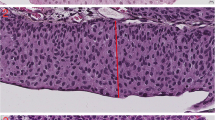

Surprisingly, the parameter most associated with grade was the 10th percentile of the nuclear area. This parameter was in fact smaller in high grade tumors, meaning that the higher the tumor grade is, the smaller is the cells area in the 10th percentile. The mean of 10th percentile nuclear area was 52\( \mu \text{m}\)2 for tumors in grade group 5, which was significantly smaller compared to tumors in grade group 3 (110\( \mu \text{m}\)2, p < 0.01) and tumors in grade group 1 (152\( \mu \text{m}\)2, p < 0.01). Looking at the images we have noticed that the reason for this unexpected finding is that high grade tumors tend to have inflammatory cells (lymphocytes and neutrophils) infiltrating between tumor cells, a finding that was almost not seen at all in low grade tumors. This correlation between higher tumor grade and lower 10th percentile of nuclear area was with the highest agreement rate of 94.5% (Fig. 5).

The parameter of the 10th percentile of nuclear area compared to the grading scores of the pathologists. There was a correlation between higher grade score and lower 10th percentile of nuclear area (a), a finding that was explained by the presence of intense inflammatory cells infiltrating between tumor cells (b)

In the training cohort, all ten cases of LGUC had almost no inflammatory cells, and only one out of the ten cases of HGUC had almost no inflammatory cells, with the other nine cases showing inflammatory infiltrate. Chi-square test showed that this difference was statistically significant (p < 0.01). In the validation cohort, seven out of ten (7/10) cases of HGUC had inflammation, and one out of ten (1/10) cases of LGUC had inflammation. Chi-square test also showed that this difference was statistically significant (p < 0.01). We have further tested the correlation between tumor grade and inflammation on a total of 100 cases by testing additional new 60 cases (30 HGUC and 30 LGUC) for the presence of inflammation. In the additional 30 HGUC cases, 19 had inflammation (19/30), and only six out of the thirty cases (6/30) of LGUC had inflammation. In the overall 100 cases, there were 35/50 HGUC with inflammation and 7/50 LGUC cases with inflammation. Chi-square test showed that the correlation between high grade and inflammation was statistically significant (p < 0.01).